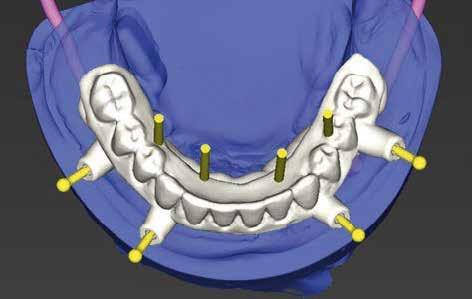

Bevezetés

Az azonnali, implantátumokkal megtámasztott teljes íves fogpótlások jól bevált, és egyre inkább elfogadott kezelési módot képviselnek a teljesen fogatlan betegek rehabilitációjában.1,2 Az ilyen típusú helyreállítások esetében átlagosan 5 éves követési időszakban 98%os túlélési arányról számoltak be.3 Az alsó állkapocs kedvező csontminőségnek és anatómiának köszönhetően az azonnali teljes ívek helyreállítása még nagyobb sikerarányt mutatott.4 A digitális technológiák, mint például a sablonnal végzett implantátumbeültetés és a számítógéppel segített protézistervezés és gyártás, képesek megkönnyíteni a diagnózist, a kezelés megtervezését és jelentősen javítják a sebészeti beavatkozásokat, ezáltal kiszámíthatóbb és hatékonyabb kezelést biztosítanak.5,6 Különösen a bonyolult sebészeti eljárások – mint például a teljes ív rekonstrukciója – jelentős mértékben profitálhatnak ezekből az előnyökből, amelyek csökkenthetik a kezelés idejét és az invazivitást a beteg számára.5,7

A digitális technológiákhoz való hozzáférést az anyagi és időkorlátok akadályozhatják, valamint az ilyen technológiákhoz kapcsolódó meredek tanulási görbe.8,9 A közelmúltban a digitális munkafolyamatok elérhetővé váltak egy kihelyezett szolgáltatás részeként: Smile in a Box (Straumann). Ez segíthet a hagyományos munkafolyamatokat használó szakembereknek, hogy könnyen élvezhessék a digitális technológiák előnyeit anélkül, hogy először le kellene küzdeniük az első hozzáféréssel járó akadályokat. Ez az esettanulmány egy hagyományos teljes fogsor sikeres azonnali átalakítását írja le azonnali teljes ívű restaurációvá a Smile in a Box által biztosított kiszervezett, teljesen digitális munkafolyamat alkalmazásával. A Straumann Pro Arch protokoll alkalmazása a Smile in a Box funkcióval kombinálva lehetővé tette számunkra, hogy könnyen hozzáférhessünk egy teljesen digitális munkafolyamathoz, amely hatékonyan integrálható a hagyományos protetikai munkafolyamatunkba, továbbá rendkívül kielégítő klinikai eredményt biztosít.

Klinikánkon egy teljesen fogatlan, hagyományos akrilát fogpótlással helyreállított 65 éves férfi beteg jelentkezett, aki nem kielégítő alsó fogsorretencióra és az azzal járó problémákra panaszkodott, beleértve a kifejezetten az alsó fogsorához kapcsolódó gyenge beszéd és rágásfunkciót. A klinikai vizsgálat gömbölyűtől a késhegyig terjedő mandibulagerinc formát és megfelelő vertikális, de nem megfelelő vízszintes csontmennyiséget állapított meg, különösen a hátsó területen (1. ábra) 10

A diagnosztikai panoráma röntgenfelvételen a mandibula íve mérsékelt IIIIV. osztályú atrófiával és megfelelő térfogatú, viszonylag sűrű III. típusú kortikális csonttal jelentkezett az interforaminális területen (2. ábra).

A hagyományos teljes kivehető fogpótlási technikákkal a kezelési stratégia a felső és alsó állcsont kapcsolatának és az okkluzális vertikális dimenzió és a fog helyzetének meghatározását foglalta magában, majd az alsó rögzített restauráció előállításához ezeket használták fel referenciákként (3. ábra) 11